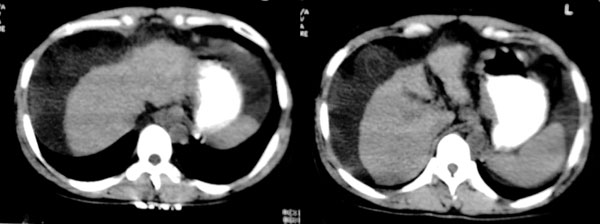

患者:女,43岁,自觉全身肿胀8个多月。b超提示:肝硬化、腹水,胆囊炎。胰、脾、肾未见明显异常。

肝脏形态不正常,比例失调,肝裂增宽,应该是肝硬化、腹水、脾脏稍大。

肝脏体积变小,左右比例失调,右肝变小较剧,脾脏增厚,腹水征象明显考虑肝硬化、腹水

大家好,还有就是她的胆囊在哪?那肝右前间隙液体内环状稍高密度是什么,又为什么壁欠光滑.请大家再帮忙看看.

肝脏体积变小,左右比例失调,右肝变小较剧,脾脏增厚,腹水征象明显考虑肝硬化、脾大,腹水。病理性胆囊[胆囊小,比增厚]

支持肝硬化、腹水、脾稍大。肝脏与前腹壁的环状影考虑是胆囊及胆囊结石。

肝右前方就是胆囊,胆囊小,壁增厚。

肝脏体积缩小,左右肝比例失调,轮廓不规整,肝裂增宽,肝周见新月形液性密度影,脾脏增厚.应诊断为肝硬化,腹水,脾大.